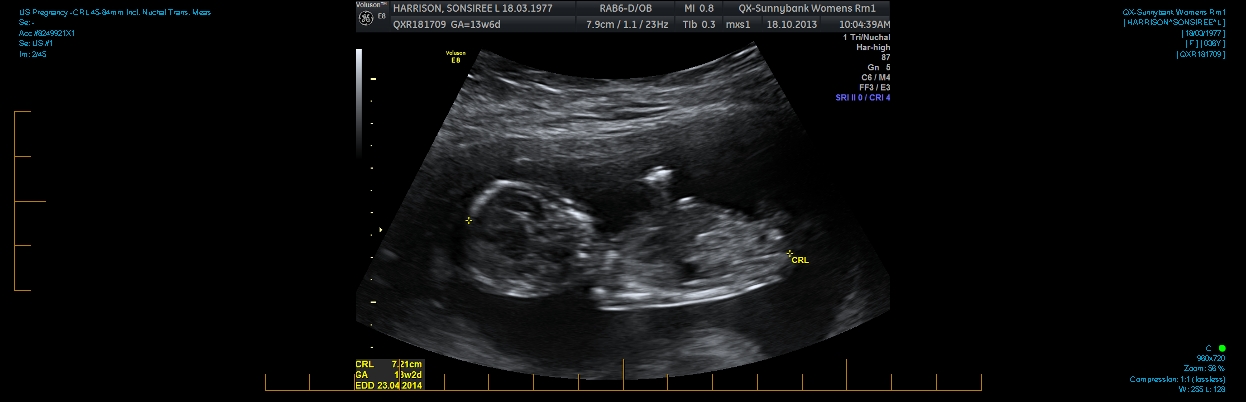

Hi everyone. I am 13w2d and can't figure out if there is a nub in these pics. I also have a potty shot. I know at this age they all have a little something. Can anyone tell me if it is prominent enough to say one way or the other?

Attachment 14828Attachment 14829Attachment 14831Attachment 14832Thanks in advance.